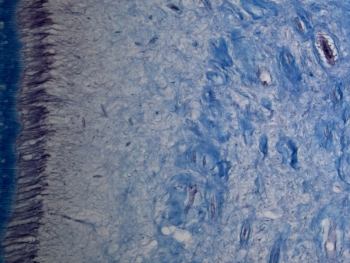

Od-20 Diente desmineralizado longitudinal (Tricrómico de Masson)

Visión general: se trata de un corte similar al anterior, pero en el que hemos realizado una tinción de tricromico de Masson. Vemos, al igual que antes en superficie a nivel coronario la dentina, ahora de color azulado, que se continua con la dentina radicular que van a rodear a la cámara y los conductos radiculares que contienen el conjuntivo pulpar de un color muy pálido. A nivel de la raíz cubriendo a la dentina vemos el cemento, también intensamente teñido de azul.

Visión específica: estructuras similares a las del preparado anterior puesto que se trata de una muestra equivalente y en la que según la zona de estudio observamos y hemos de analizar las diferentes estructuras: cemento, dentina y la pulpa. Estudiar las variaciones cromáticas que se dan con la utilización del tricrómico y nos van a permitir estudiar mejor algunas cuestiones estructurales de los tejidos dentarios y peridentarios.